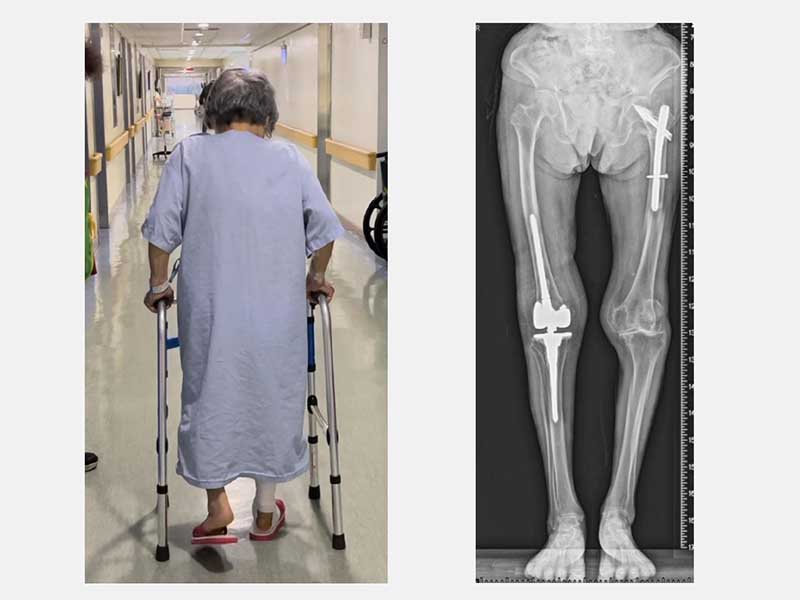

由於老太太的骨質疏鬆嚴重,不僅是粉碎性骨折也連帶傷到膝關節的韌帶。黃部長使用新式預鎖式樞紐設計的人工關節,可以取代韌帶的功能也可填充骨頭缺損來重建一個穩定的膝關節。老太太手術當天下午就可以自己拿著助行器下床上廁所。此外,從手術隔天開始,除了骨質疏鬆症的治療,還搭配手術後疼痛中醫輔助醫療,復健科醫師也根據老太太的需求安排復健運動,在病床邊開始固定式腳踏車訓練。在手術後第5天,老太太開心的出院走路回家。

隨著台灣進入超高齡社會,罹患退化性關節炎的民眾逐漸增加。近年來不僅接受手術年齡層越來越高,有多重內科疾病和像黃老太太一樣有嚴重骨質疏鬆症的老人家也越來越多。目前該院使用微創人工關節手術技術搭配「怡樂適(ERAS)手術加速康復療程」,不僅讓病人恢復快、降低術後併發症風險也大幅縮短住院時間。現在更加入手術後疼痛中醫輔助治療,即便是近百歲人瑞也能透過多專科團隊合作提供成功治療回到日常生活。黃部長建議民眾應該及早尋求專業骨科醫師的意見,進一步檢查與治療,開心地享受健康人生。